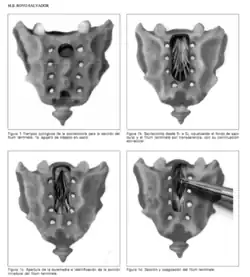

Sección del Filum Terminale

Si la causa de la escoliosis se basa en una lesión neurológica (tensión anómala del filum terminale) y no en las puramente mecánicas (que serían sus efectos) el neurocirujano puede intervenir. El tratamiento que desde 1993 está dando unos resultados esperanzadores es la Sección del Filum Terminale (SFT),[35] ya que atacaría directamente la causa de la enfermedad y no solo sus efectos. Este tipo de intervención varía sus resultados en función del grado de afectación de desviación de la columna, detendría su progresión y puede mejorar el desvío de la columna vertebral especialmente si va acompañada de un adecuada fisioterapia. El tratamiento se realiza bajo anestesia local y sedación. El paciente no precisa corsé de corrección si las curvaturas son menores de 35-40º.